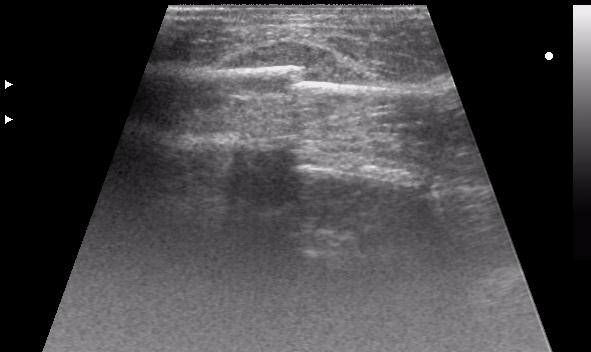

УЗИ- перелом ключицы (когда в рентгене очередь...)

перелом ключицы, большой отек, травматолог хотел определится с тактикой...

по первому скану: перелом получается множественный? - кроме линии перелома впечатление о нарушении заднего контура ближе к границе среза (правда не в фокусе)